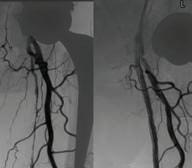

In 2023, there was a 9% increase in cases of Syphilis < 2 years of duration in Australia. This increase is of concern, as a baby can contract congenital syphilis through transplacental transmission. The transmission rate is highest (60-90%) during untreated primary and secondary syphilis.

Testing during pregnancy: Offer routine syphilis testing at the first antenatal visit. Recommend follow-up testing at 28–32 weeks, dependent on local guidelines.